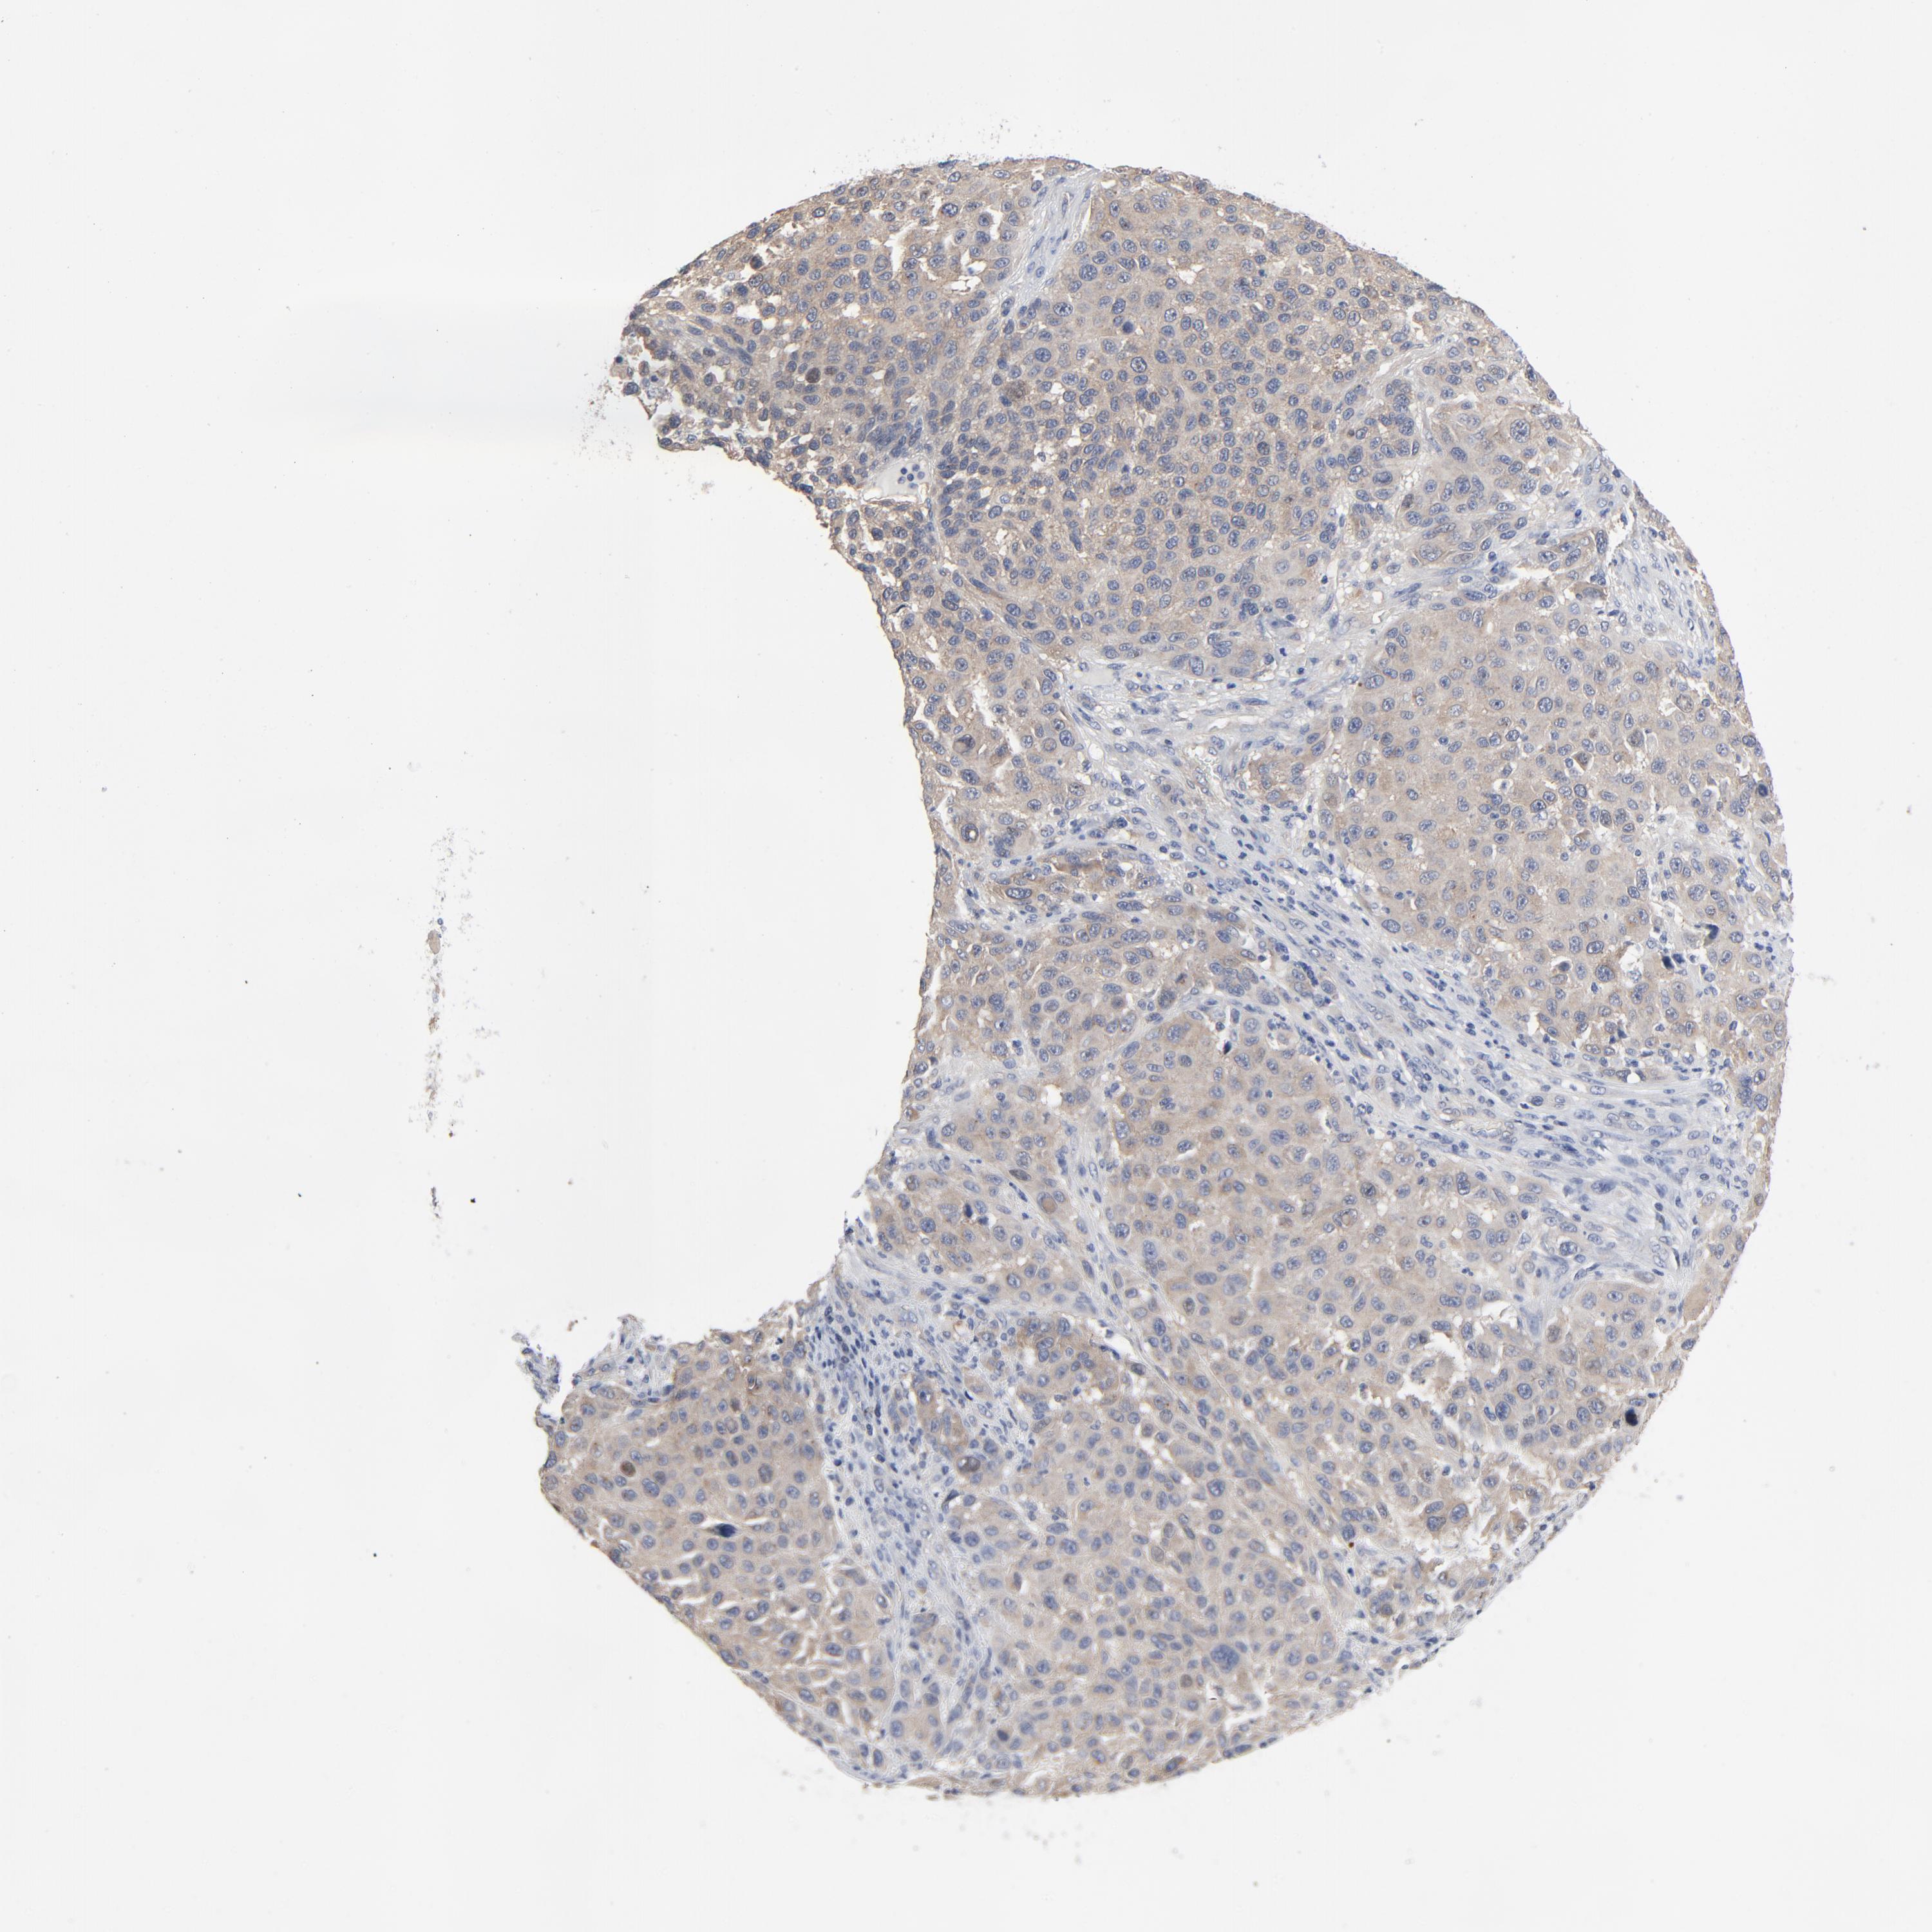

MELANOMA - Protein expressioni

A mouse-over function shows sample information and annotation data. Click on an image to view it in a full screen mode. Samples can be filtered based on level of antibody staining by selecting one or several of the following categories: high, medium, low and not detected. The assay and annotation is described here.

Note that samples used for immunohistochemistry by the Human Protein Atlas do not correspond to samples in the TCGA dataset.

Antibody stainingi

Antibody staining in the annotated cell types in the current human tissue is reported as not detected, low, medium, or high, based on conventional immunohistochemistry profiling in selected tissues. This score is based on the combination of the staining intensity and fraction of stained cells.

Each image is clickable and will lead to virtual microscopy that enables deeper exploration of all samples and also displays staining intensity scores, fraction scores and subcellular localization as well as patient and tissue information for each sample.

Antibody HPA003938

Staining

High

Medium

Low

Not detected

Intensity

Strong

Moderate

Weak

Negative

Quantity

>75%

75%-25%

<25%

None

Location

Nuclear

Cytoplasmic/membranous

Cytoplasmic/membranous,nuclear

Malignant melanoma, NOS

Malignant melanoma, Metastatic site